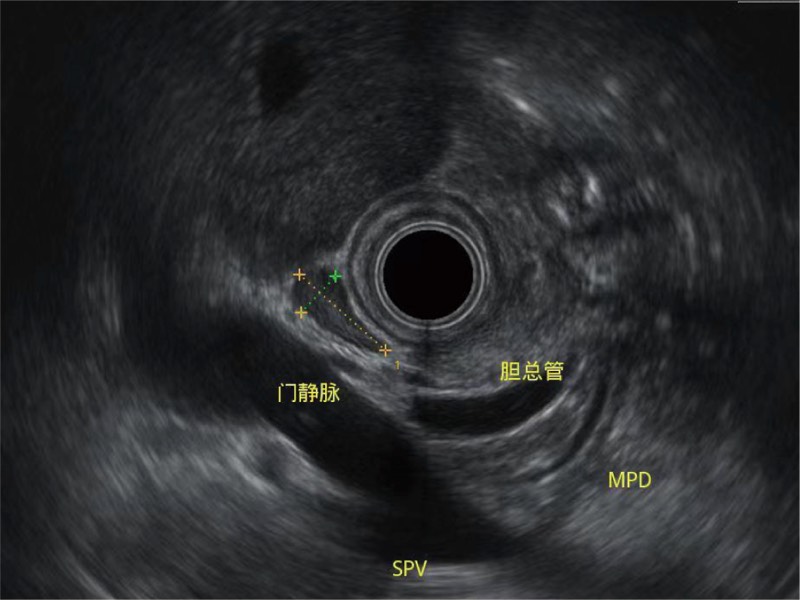

肝左叶和肝静脉的横截面